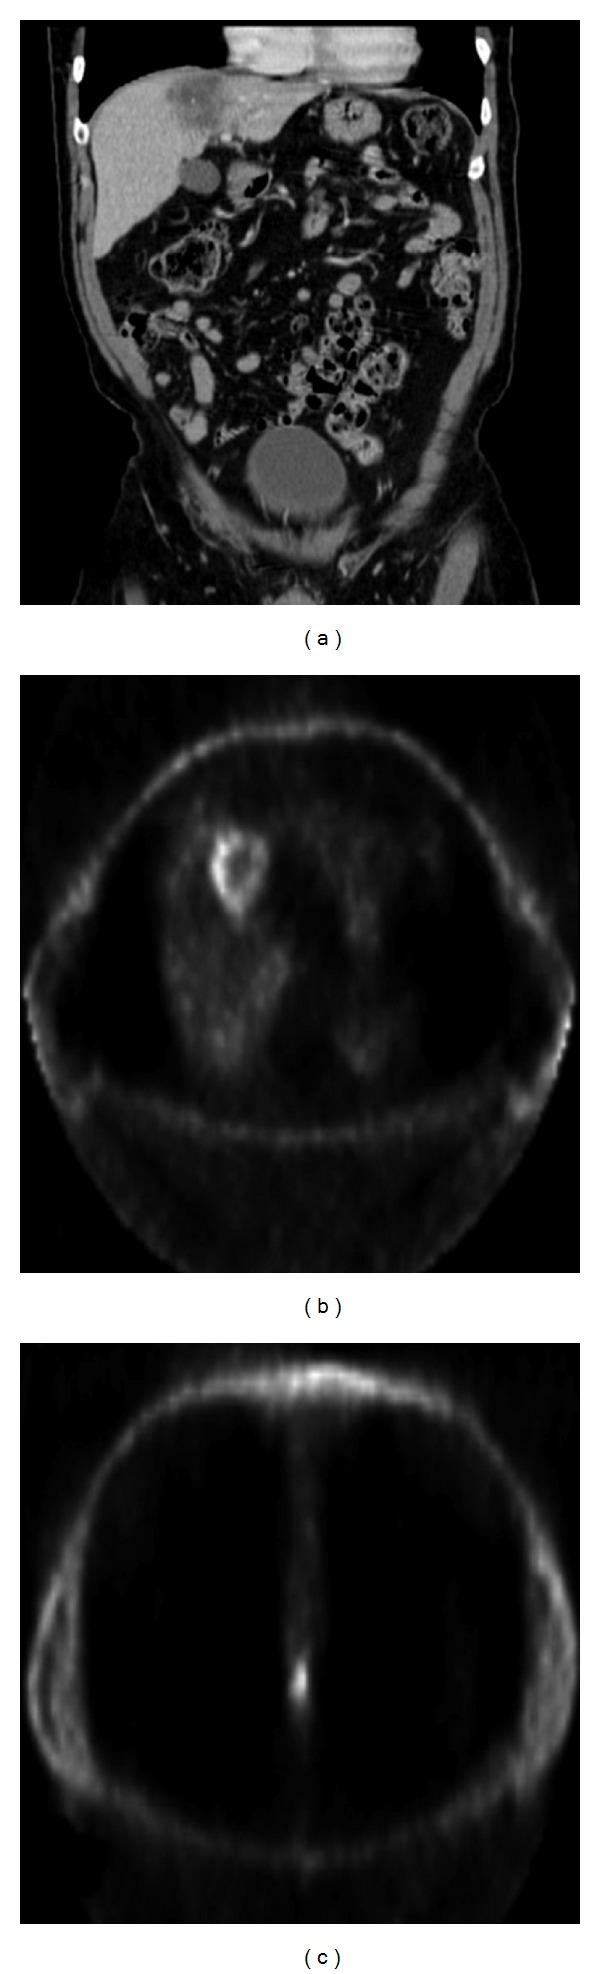

Squamous cell carcinoma of the anus is a relatively uncommon GI malignancy. When it does occur, it metastasizes in only a small minority of patients. Spread of anal squamous cell carcinoma to the brain is exceedingly rare, and has been previously reported only three times in the medical literature. We report the case of a 67 year old male who was diagnosed on presentation with a poorly differentiated anal squamous cell carcinoma that already had a solitary metastasis to the liver. While the tumors were initially responsive to chemoradiotherapy, the patient's primary and liver lesions recurred. The patient then underwent synchronous abdominoperineal resection for the primary lesion and a liver lobectomy for the metastasis. Soon thereafter, the patient developed focal neurologic symptoms and was found to have an intracranial lesion that on biopsy demonstrated metastatic squamous cell carcinoma. This case highlights the fact that patients with a previous history of anal squamous cell carcinoma can occasionally develop cerebral metastasis. Furthermore, cerebral metastases from anal squamous cell carcinoma portend a dismal prognosis even in the face of aggressive medical and surgical therapy.

肛门鳞状细胞癌是一种相对罕见的胃肠道恶性肿瘤。当它确实发生时,只有少数患者会发生转移。肛门鳞状细胞癌扩散至脑部极为罕见,此前医学文献中仅报道过3次。我们报告一例67岁男性病例,该患者初诊时被诊断为低分化肛门鳞状细胞癌,且已出现肝脏孤立转移灶。虽然肿瘤最初对放化疗有反应,但患者的原发灶和肝脏病灶复发。随后患者接受了原发灶的同期腹会阴切除术和转移灶的肝叶切除术。此后不久,患者出现局灶性神经症状,经检查发现颅内有一病灶,活检显示为转移性鳞状细胞癌。该病例凸显了既往有肛门鳞状细胞癌病史的患者偶尔会发生脑转移这一事实。此外,即使面对积极的药物和手术治疗,肛门鳞状细胞癌的脑转移预后也很差。